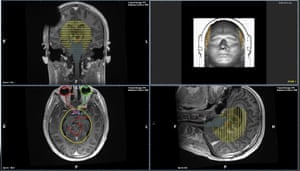

Raj Jena, en neuro-onkolog på Addenbrooke ‘ s hospital i Cambridge, har trukket op, det billede til at forklare, hvordan læger planlægge strålebehandling til patienter. For i en sag som denne, at han måske er nødt til at studere mere end 100 billeder, der hver viser en tynd skive af hjernen. Derefter, billede af billede, Jena, skal nøje mærke ud for kanten af tumor, og konturerne af følsomme områder af hjernen, der bør blive sparet for strålebehandling bjælker: hypothalamus, hypofysen, veje til hjernen ‘ s vision centre, for eksempel. Processen kan tage flere timer. Men først når det er gjort, kan computere begynde at beregne, hvordan at ramme tumor med strålebehandling bjælker uden frazzling vigtige dele i nærheden.

En planlægning MR-scanning viser, at hjernen hos den unge patient med en aggressiv hjernetumor. Foto: Cambridge University hospitals NHS foundation trust

Med kunstig intelligens (AI), den vanskelige opgave kan udfyldes på få minutter. For de seneste seks måneder, Jena har brugt et Microsoft-system, der kaldes InnerEye til at markere scanner automatisk for prostatakræft-patienter. Mænd udgør op mod en tredjedel af den 2.500 kræftpatienter hans afdeling behandler hvert år. Når en scanning er udført, billederne er anonymiseret, krypteret og sendt til InnerEye program. Den beskriver de prostata på hvert billede, skaber en 3D-model, og sender oplysningerne tilbage. For prostata kræft, hele organet er bestrålet.